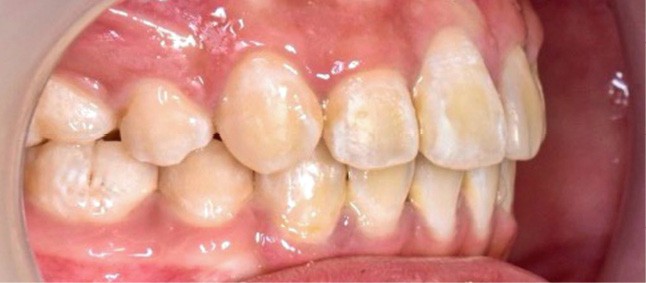

Une patiente âgée de 12 ans se présente en consultation, motivée par la position de son incisive centrale maxillaire, décrite comme « en avant », marquée par une dyschromie et une mobilité de grade 2 selon Muhlemann. L’examen clinique montre l’absence de 23 sur l’arcade, une dysharmonie dents-arcade marquée, un surplomb accentué, et une déviation des milieux inter-incisifs, conséquence du comblement spontané de l’espace de 23. L’ensemble s’inscrit dans un contexte de Classe I d’Angle molaire. L’orthopantomogramme révèle l’inclusion de 23, associée à une résorption radiculaire étendue aux deux tiers de 21. La 22 ne présente aucune altération visible.

La patiente, de profil normodivergent, présente une Classe I squelettique sans troubles fonctionnels (fig. 1-8).